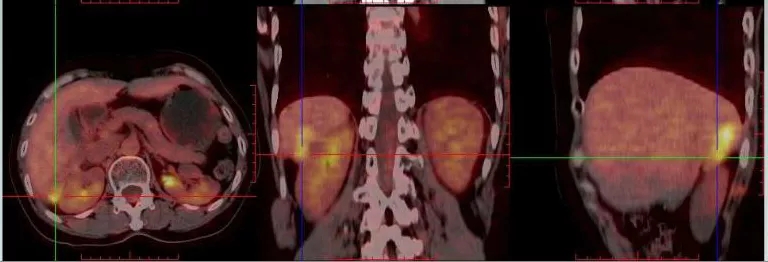

2013.5.10 PET-CT:肝肾隐窝、脾肾间隙、脾门旁、腹膜后可见斑片状、囊实性及结节状影,实质部分FDG代谢增高,考虑转移。

2013.5.10 PET-CT检查结果